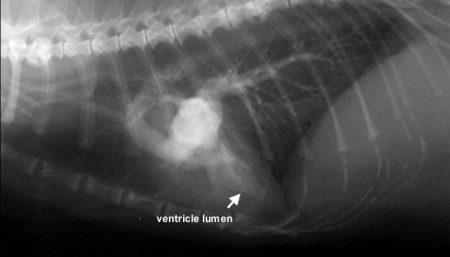

• Genetinės ligos. Jie yra dažniausios kardiomiopatijos priežastys. Britų mokslininkų 2017 m. Atlikti tyrimai parodė, kad kardiomiopatija serga apie 10% Birmos kačių. Dažniausia yra hipertrofinė kardiomiopatija, kuria serga beveik 7% šios veislės.